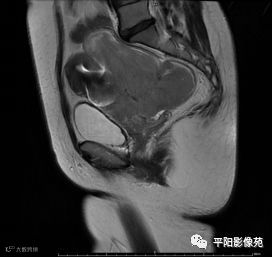

MRI表现

T2轴位

(宫腔内见金属节育环伪影)宫颈区见不规则形等T1稍长T2信号软组织肿块,DWI序列呈明显高信号,大小约为3.87cmX2.64cm,双侧宫颈基质低信号环连续性中断,病灶向子宫右后上方生长,周围脂肪间隙模糊,增强扫描明显强化,强化程度低于子宫及宫颈实质;子宫后方、子宫直肠间隙见不规则形长T1长T2信号软组织肿块,DWI序列呈高信号,大小约10.12cmX4.82cmX10.29cm,病灶呈分叶状,向下方生长与宫颈分界不清,与直肠分界尚清,增强扫描明显不均匀强化。